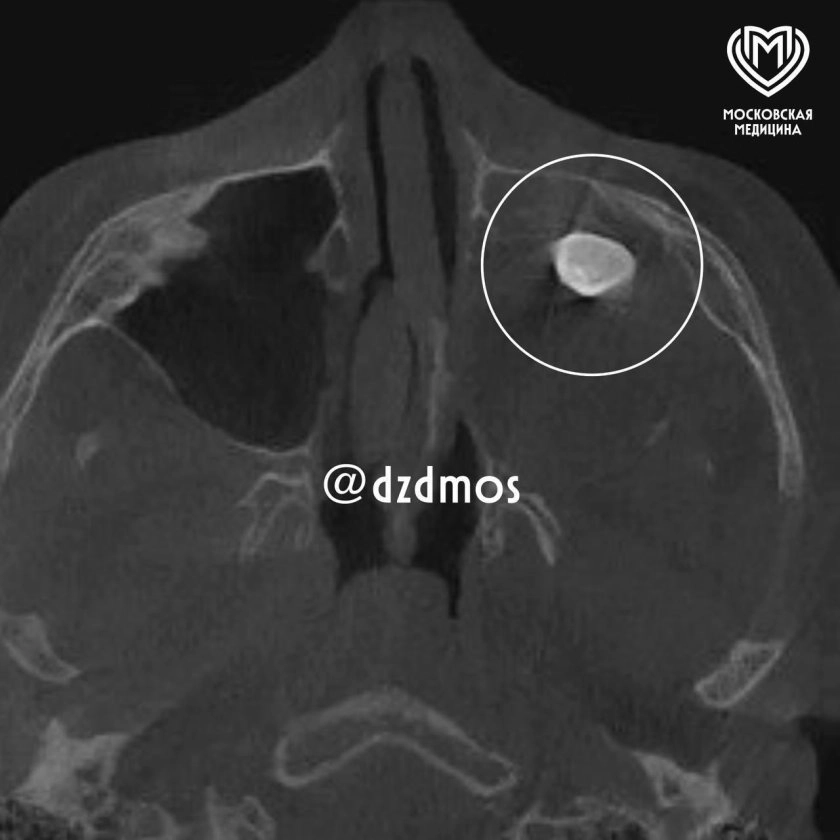

Врачи столичной больницы обнаружили у 15-летнего пациента редкую патологию. Причиной заложенности носа и асимметрии лица оказался зуб, который рос в гайморовой пазухе, а не в челюсти.

В ходе операции хирург-оториноларинголог Вугар Достиев вскрыл гайморову пазуху и обнаружил новообразование. Внутри этой доброкачественной опухоли (тератомы) и находился полностью сформировавшийся зуб. Медики аккуратно удалили его.